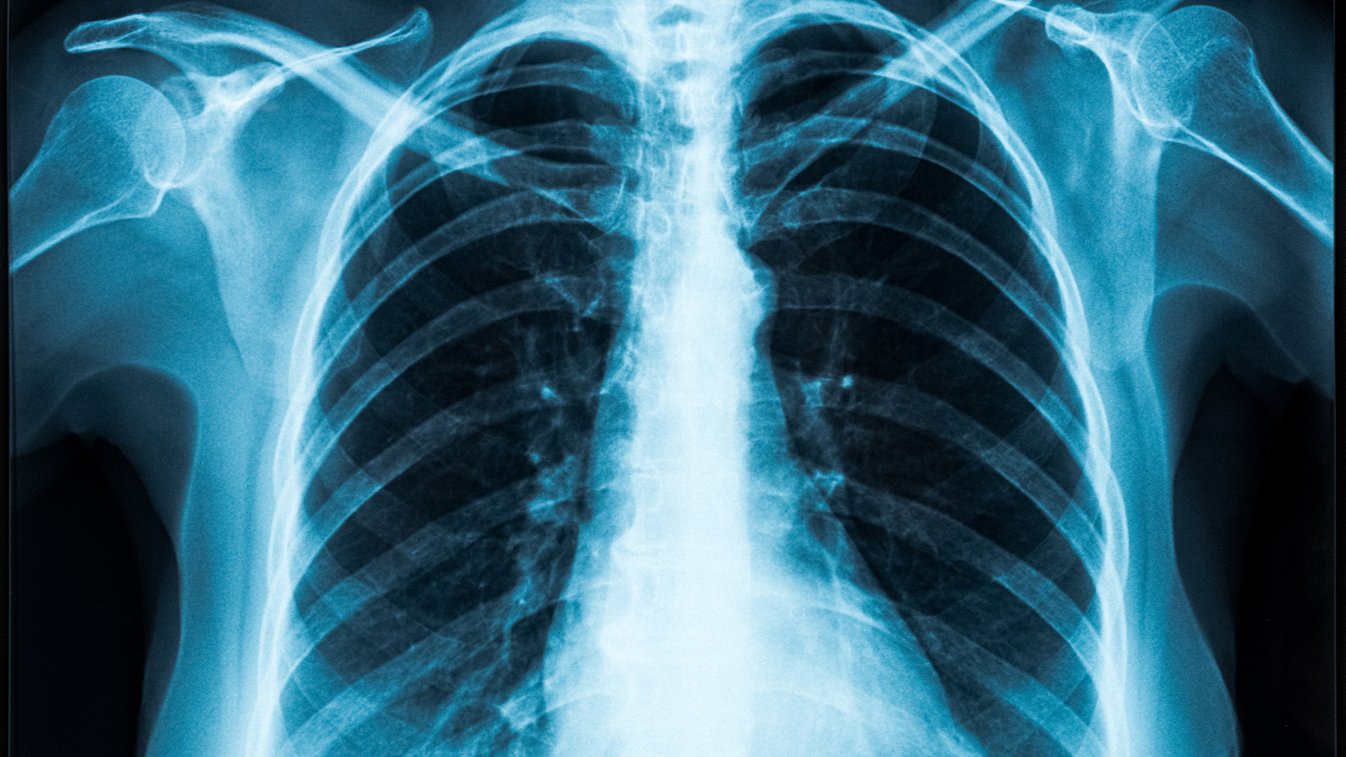

التليف الرئوي.. ما أسبابه؟ وهل من علاجات واعدة؟